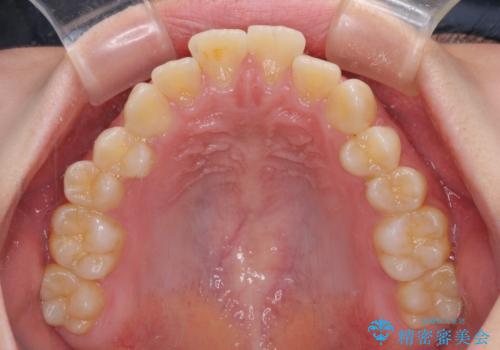

口元が引っ込みすぎることもなく、上下前歯がきれいに接触する位置に仕上げることができました。

横顔に出っ歯の印象はありませんでしたが、下顎のスペースと上下前歯の前後位置の大きなズレを改善するために、上顎左右の第一小臼歯2本を抜歯しすることとしました。

口元が引っ込みすぎないようにするために、上下ともに臼歯を前方に移動させる必要があり、インビザラインでは対応できないため、表側のワイヤー装置にて矯正治療を行うこととしました。